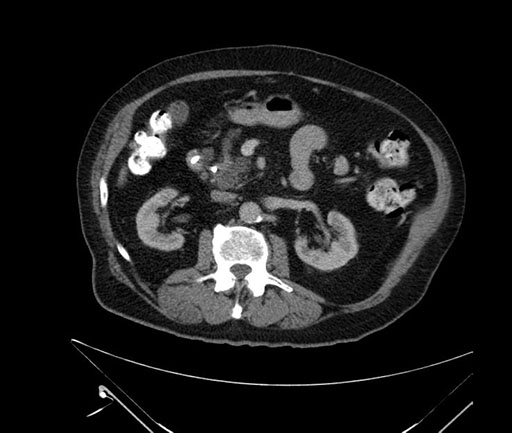

Whipple (pancreaticoduodenectomy) [case 7]

Axial - 3 months prior

Imaging analysis

Based on your CT findings, which issue(s) would give reason for "planned slowing down moment(s)" in this case?

Considering a standard Whipple procedure, what step(s) of the operation would you do differently in this case?